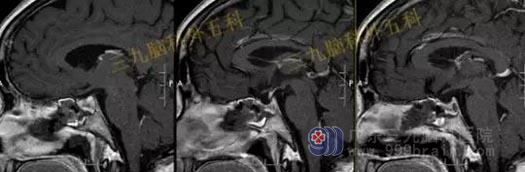

头部MR检查提示:

鞍区占位,现:鞍内垂体前叶示一类圆形异常信号,呈各序列内低外高信号影,增强后未见强化,范围约为1.2cm×1.2cm×0.7cm,视交叉略受压,大致同前。

手术过程:内镜下经鼻蝶鞍区rathke囊肿切除术,术中打开鞍底,保护正常垂体,在下方最薄弱上台垂体,可见胶冻样囊液,给予全切,术中垂体、鞍膈保护良好,无脑脊液漏形成。

术后复查头部MR检查提示:经鼻蝶鞍区占位性病变切除术后改变,原病灶已切除。

头部MR检查提示:鞍上区-桥前池见一不规则囊性病变,T1WI呈低信号,T2WI呈高信号,FLAIR呈低信号,增强扫描前缘可疑斑片状强化,病灶范围约2.9cmx3.9cmx3.1cm,视交叉受压向前上方移位,脑干、双侧颞叶内侧受压,幕上脑室系统扩大,脑池、脑沟未见增宽,中线结构居中。

手术过程:内镜下扩大经鼻蝶入路,行鞍上区颅咽管瘤切除术+颅底重建术,术中肿瘤切除,垂体及垂体柄、视神经及视交叉、双侧颈内动脉保护良好,腹部脂肪及鼻中隔粘膜瓣修补鞍底。

术后复查头部MR检查原病灶已切除。